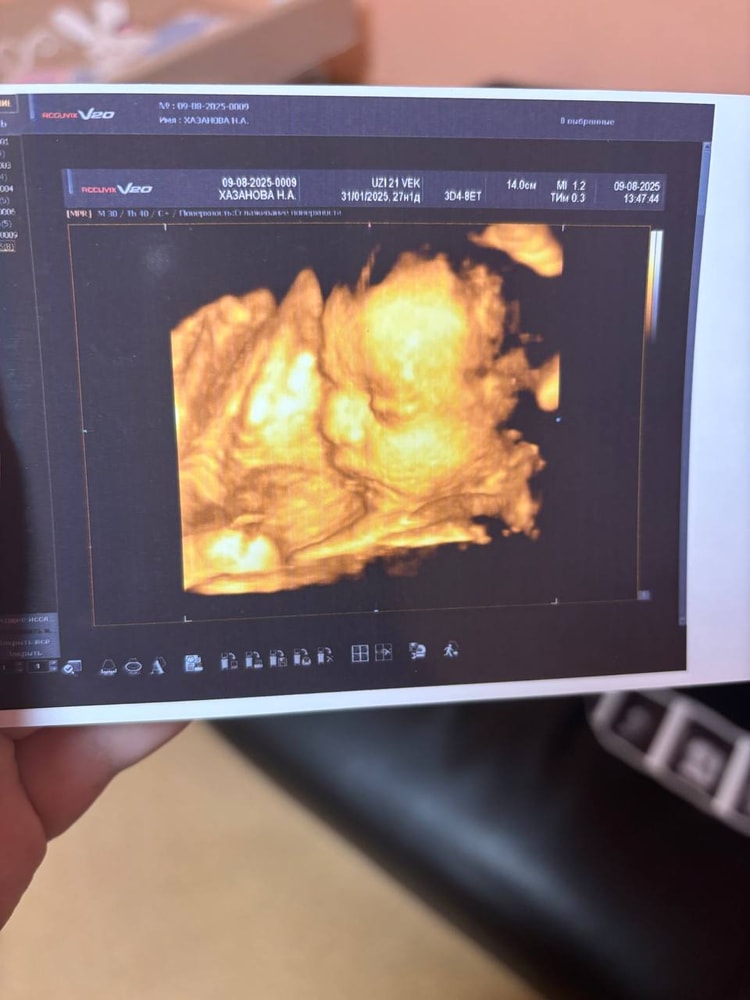

УЗИ, КТГ, доплерВ субботу ходили на 4Д УЗИ. Срок на этот момент без одного дня 25 недель. Неудачно лежал, конечно, но рассмотреть все таки удалось)) И нам подтвердили пол, так как всего 1 раз смотрели на УЗИ, а ведь всякое бывает. По началу малыш вел себя спокойно, а под конец вообще потянулся и закрылся ручками, но мы успели его более-менее рассмотреть до этого момента. Носик прям мужа 100-процентный, остальное так и не разобрали где чье, да и не так важно. Эмоции у меня прям зашкаливали, а вот мужу не зашло. Крипота, говорит, ахаха. Я отчасти согласна, выглядит это и правда жутковато, но когда понимаешь, что это твой малыш, то все эти моменты на второй план уходят. Записали нам видео всего процесса, наделали много ч/б фоточек и 1 сделали цветную. Вот такой богатырек у нас подрастает))